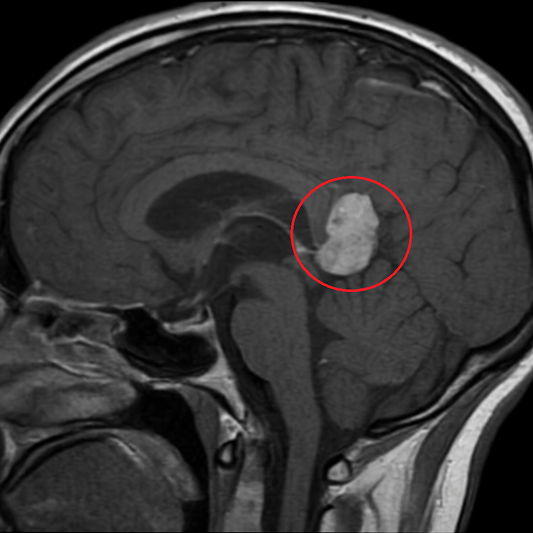

Пинеобластома — злокачественное новообразование головного мозга, для которого свойственен агрессивный и активный рост, а также метастазы. Происхождение тканей опухоли — паренхиматозные клетки эпифиза (пиноциты).

Их основу составляют нейровизуализирующие методики, которые информативны в плане роста, места расположения пинеобластомы и распространенности патологического процесса. Пациентов в основном направляют на магнитно-резонансную томографию головного мозга. Если же к МРТ существуют противопоказания, тогда показана церебральная компьютерная томография.